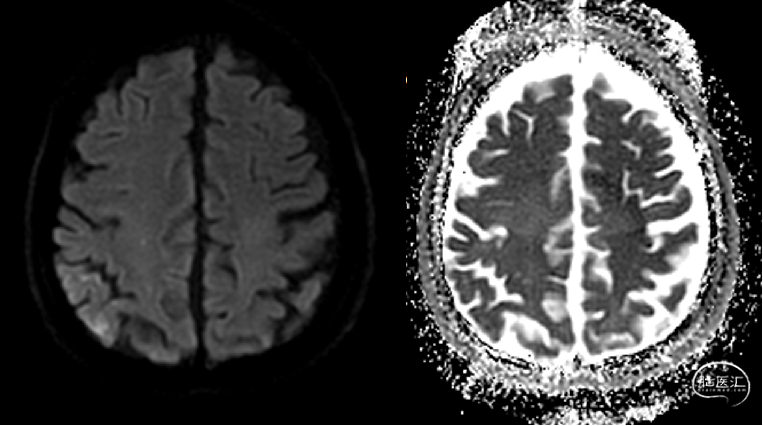

头颅核磁提示:右侧大脑半球、双侧小脑半球多发散在DWI高信号,考虑急性亚急性脑梗死;头颅MRA未发现明显重度狭窄及闭塞大血管。

急诊头颅MRA未见颅内大血管较重狭窄或闭塞。